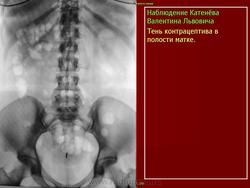

Инородные тела.

Приложения:

1.ov_.8.i.slayd7_.jpg2.ov_.9.i.slayd8_.jpg3.ov_.10.i.slayd9_.jpg